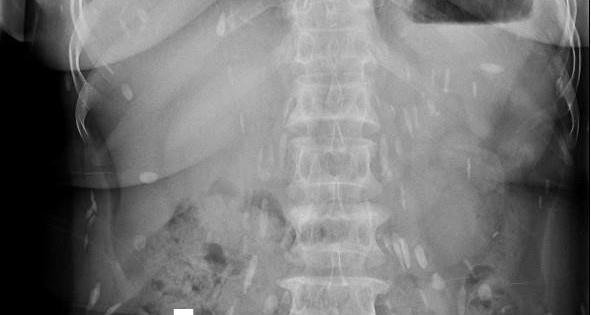

Đau nhức khắp cơ thể suốt nhiều năm, bà H đến bệnh viện khám thì phát hiện mình bị nhiễm sán lá gan, đang sinh sôi lan ra nhiều bộ phận...

Hơn 50 trẻ ở một xã của Bắc Ninh nhiễm sán lợn. Các em được gia đình đưa đi xét nghiệm ký sinh trùng sau khi bếp ăn Trường Mầm non xã Thanh Khương, huyện Thuận Thành (Bắc Ninh) bị cơ quan chức năng phát hiện dùng thịt kém chất lượng. Tuy nhiên, không chỉ món thịt lợn mà nhiều món ăn khoái khẩu của người Việt cũng có nguy cơ nhiễm sán.

Theo thống kê của Bệnh viện Bệnh nhiệt đới Trung ương và Viện Sốt rét - Ký sinh trùng - Côn trùng Trung ương, trong hai ngày 15 và 16.3, có hơn 1.500 cháu bé độ tuổi mầm non ở huyện Thuận Thành, Bắc Ninh đến bệnh viện xét nghiệm. Tính đến sáng 17.3, đã có 81 trẻ dương tính với sán lợn.